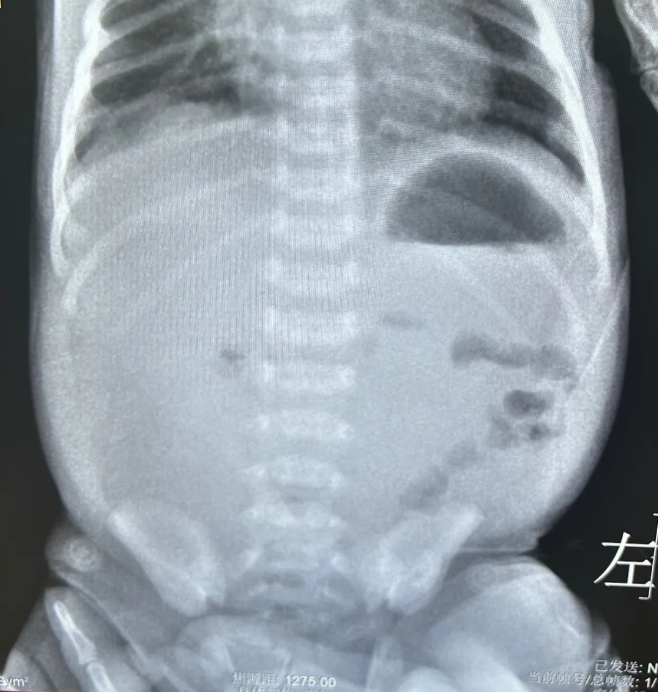

张伟主治医师与吴琼主管护师火速准备转运设备,1小时内便将贝贝安全转入科室。入院后,医护团队快速完成生命体征监测、电解质及血气分析等检查,张伟陪同患儿完成超声检查,最终确诊为先天性肠旋转不良合并肠扭转540度,手术刻不容缓。

医护团队一边安抚濒临崩溃的患儿家长,高效完成术前谈话与准备工作;一边由张艳霞与张伟联手,为贝贝实施腹腔镜肠扭转复位+Ladd's术。术中可见患儿腹腔已出现乳糜性腹水,肠系膜、肠壁附着乳糜液体,淋巴管回流异常,肠管随时面临缺血坏死的危险。